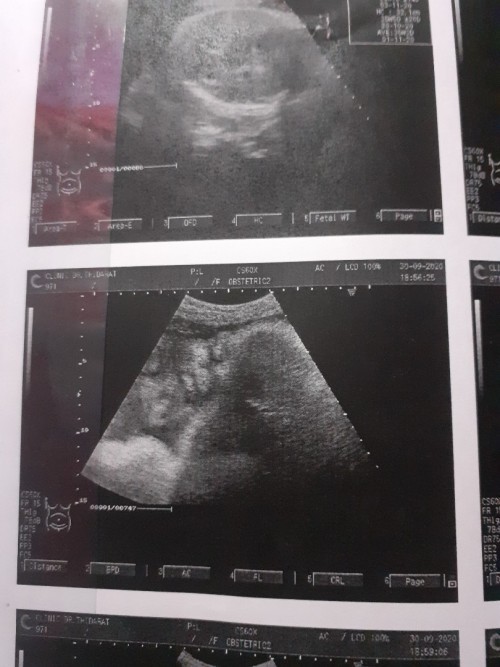

มาอวดรูปตอนซาวด์กันหน่อยค่ะ แม่ๆกำหนดคลอดเดือนไหนบ้างคะ